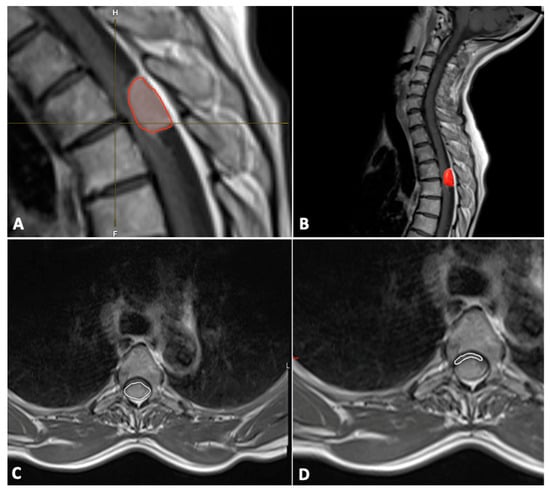

In addition, the tumor volume (mm3) was also segmented manually using Brainlab Elements® version 3.1.0 (Brainlab AG, Munich, Germany) using axial and sagittal contrast-enhanced T1-weighted images (Figure 1).

The cross-sectional area (mm2) of the spinal canal, spinal cord, and tumor were measured on the axial T1-weighted contrast-enhanced MR image at the level of maximal tumor occupancy of the spinal canal (Figure 1).

Figure 1. Tumor (red frame in the image) volume measurements with Brainlab Elements® version 3.1.0 (A,B); cross-section of spinal meningioma (C) and spinal cord (D).